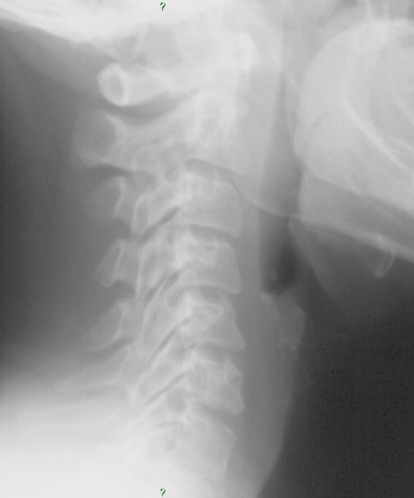

51 year old female presenting with neck pain and stiffness.  No history of trauma related by the patient. ​

1.  What are your key findings?

2.  What is your differential diagnosis?

3.  What is the appropriate follow up for this patient?